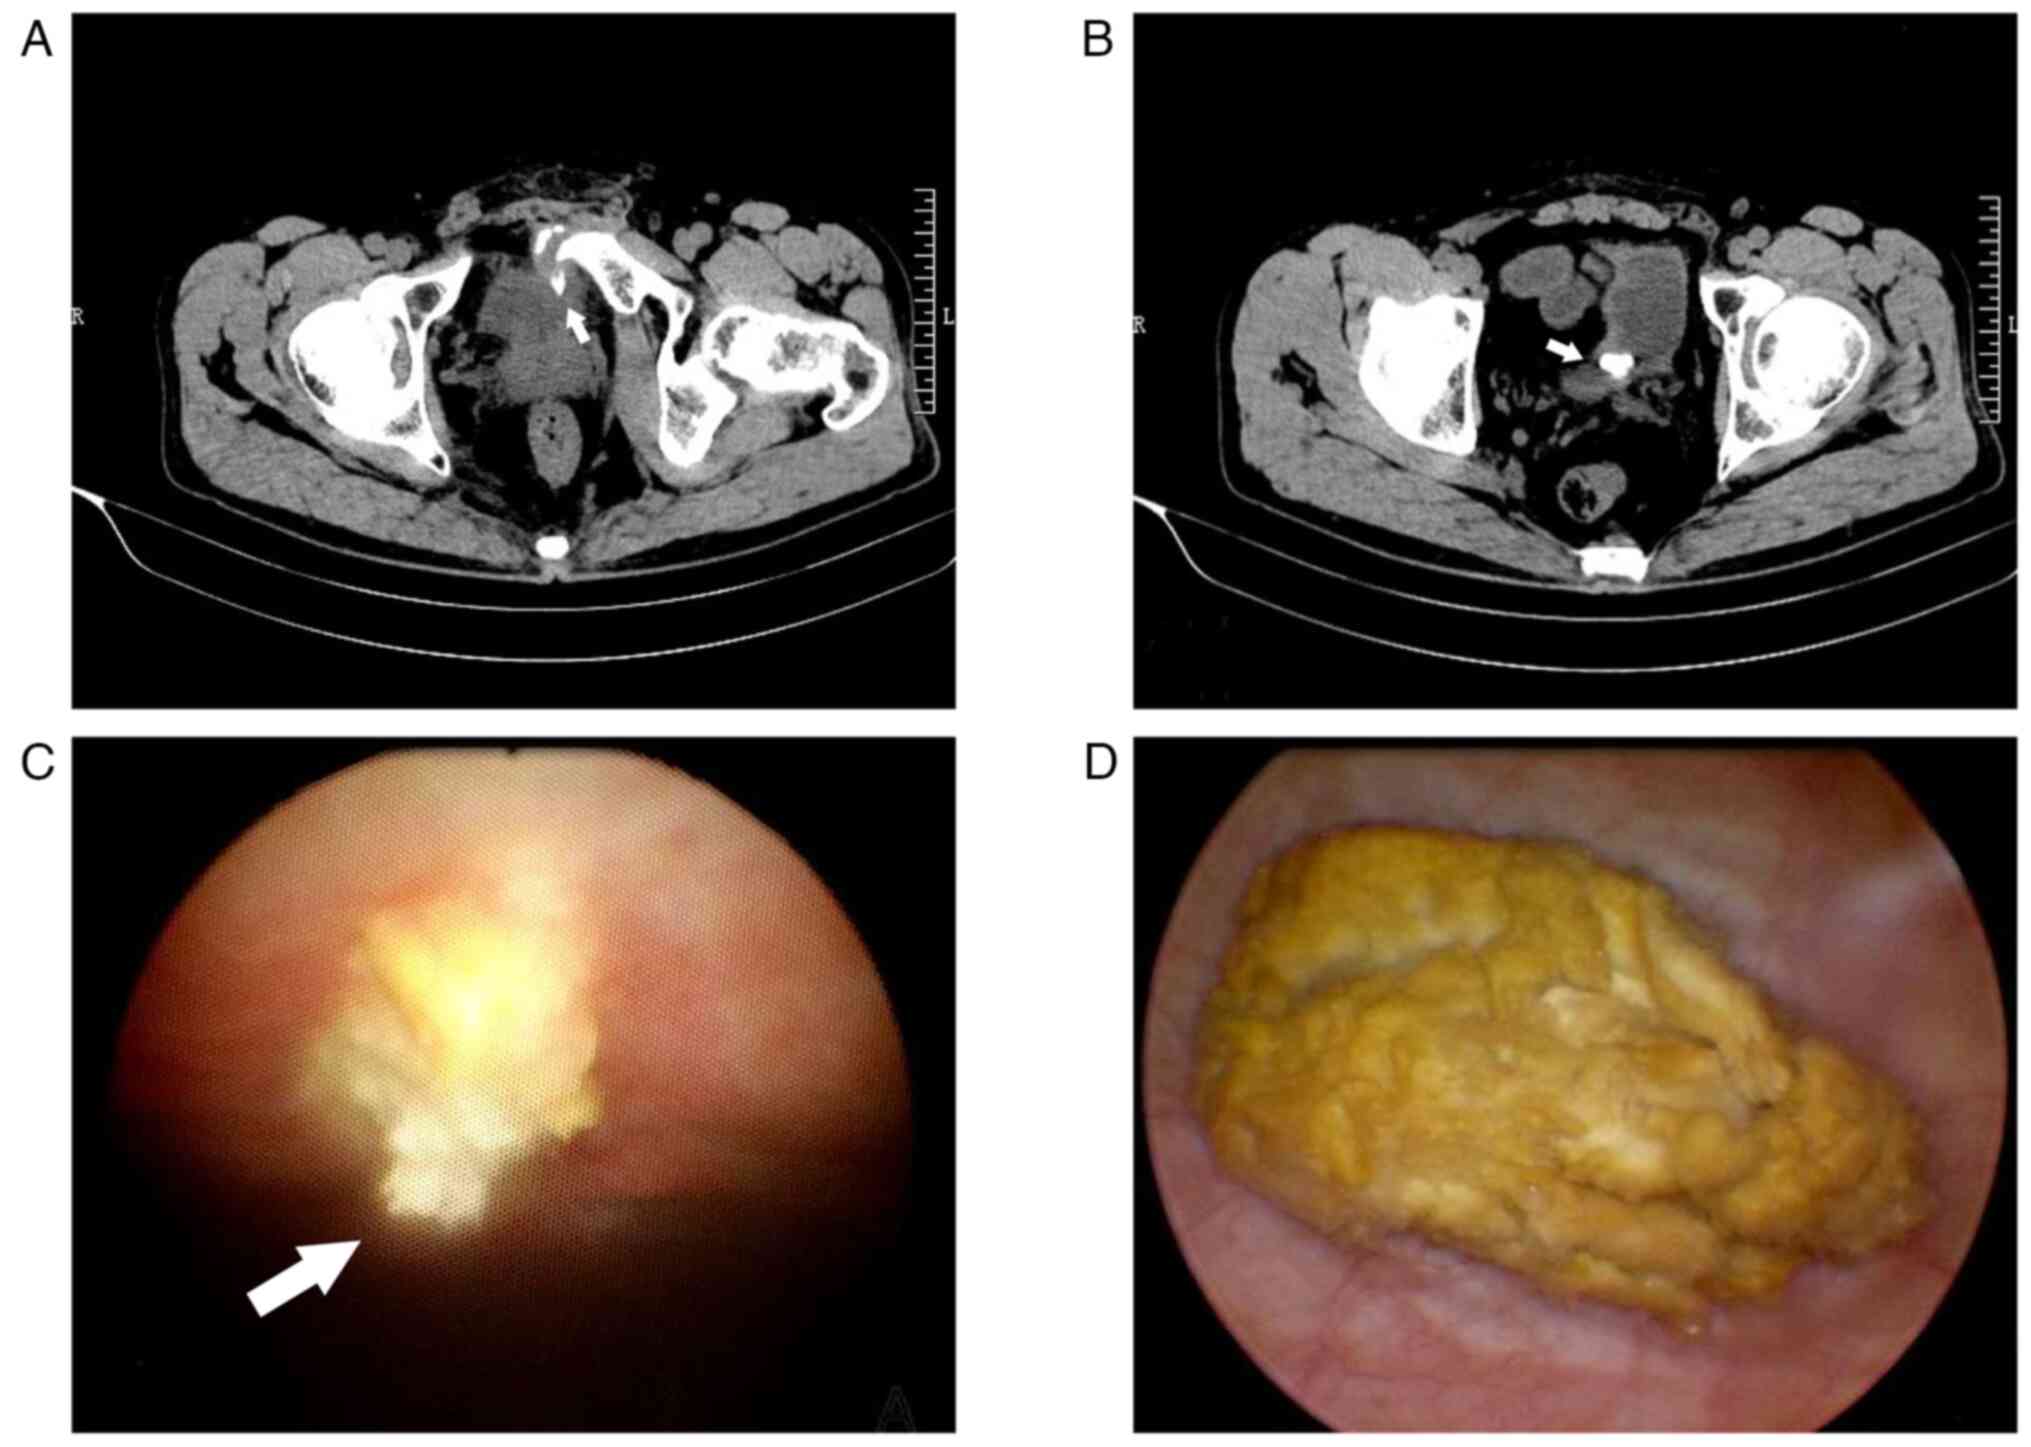

Secondary bladder stone caused by delayed penetration of the bladder by a pubic fracture: A case report and literature review

Pelvic fractures sometimes lead to injuries of the urinary bladder, which commonly present as gross hematuria, dysuria and lower abdominal pain. As a type of urinary stone, bladder stones are usually secondary to lower urinary tract obstruction, such as benign prostatic hyperplasia, urethral stricture, and neurogenic bladder. The present case report examines an unusual case of a delayed pubic fracture penetrating the bladder, which caused a secondary bladder stone. A 53-year-old man was first hospitalized at The Second Hospital of Jiaxing (Jiaxing, China) in January 2020 because of trauma-induced bleeding in the scalp and abdominal pain. The patient underwent abdominal exploration and partial bowel resection, and his condition stabilized after surgery. After discharge, the patient had regular outpatient check-ups every 2-3 weeks. However, after 3 months, in April 2020, the patient was readmitted to the hospital because of frequent urination, an urgent need for urination and dysuria. Abdominal computed tomography imaging and cystoscopy revealed a pubic fracture that had penetrated the bladder wall, accompanied by a bladder stone. Subsequently, cystolithotomy was performed, which provided significant relief of symptoms once the catheter was removed after 2 weeks. Since then, the patient has been followed up until January 2023 and had remained asymptomatic. Bladder stones caused by necrotic bone fragmentation are rare. Bladder injuries resulting from pelvic fractures can have delayed onset; therefore, clinicians should be aware of the possibility of urogenital injury in such patients. It is crucial for clinicians to comprehend the potential mechanisms involved, analyze the clinical data of patients, closely monitor their condition and implement appropriate treatment measures when necessary.